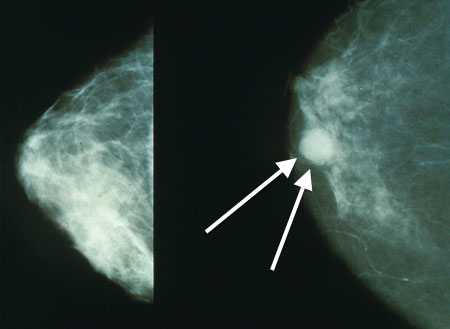

Untuk gejala kanker payudara, secara umum cukup mudah di kenali sedari dini, seperti gejala-gejala berikut ini.- Benjolan pada payudara anda berubah bentuk / ukuran.

Pada tahap awal jika anda sudah merasakan hal-hal aneh di atas terutama adanya benjolan atau tumor yang tumbuh pada payudara segeralah melakukan pemeriksaan pada dokter, agar bisa di deteksi secepat mungkin.